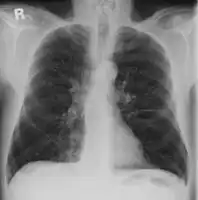

Alpha-1-antitrypsin deficiency/frontal radiograph lungs

Emphysema due to alpha-1 antitrypsin deficiency